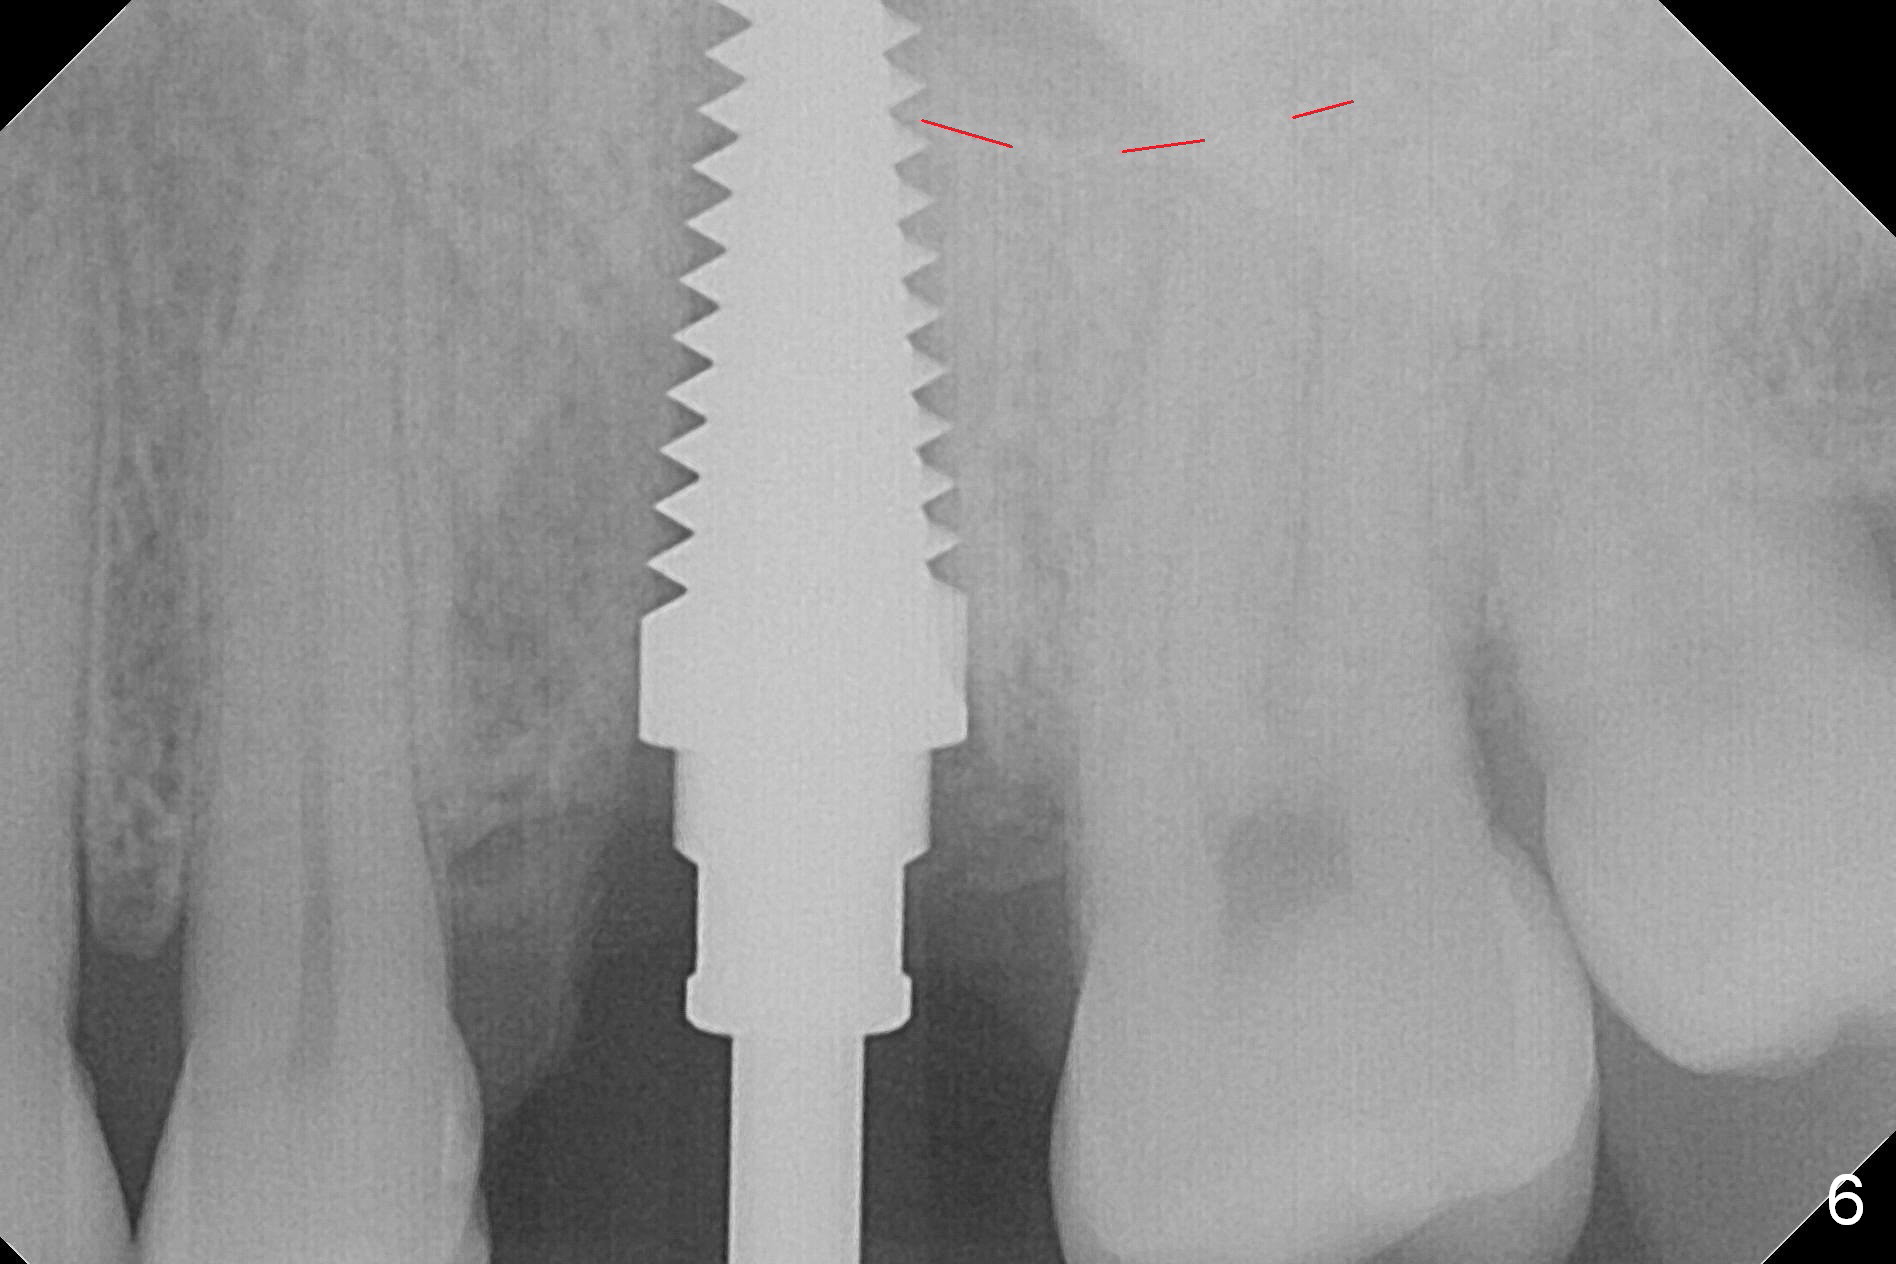

The septum perforates into the distobuccal socket when 4.3 mm drill is being used. The sinus floor bone (Fig.5 *, Fig.6-8 red dashed line) has to be used for primary stability. Finally a 6x20 mm tap achieves stability apparently by engaging to the mesial and distal walls of the socket (Fig.6). The insertion torque of a 6x20 mm tissue-level implant is > 60 Ncm (Fig.7) with allograft packed into the remaining socket (*).

A much smaller implant should be used (e.g.4.5 mm) in order to save the septum. But the apical granulation tissue above the septum cannot be removed completely. There is no bone loss around the implant 4 months postop (Fig.9), although the gingiva is unhealthy because of lack of oral hygiene locally. The immediate provisional is not reseated with oral hygiene instruction. Impression will be taken in 2 weeks. Take photos to show disappearance of the fistula.